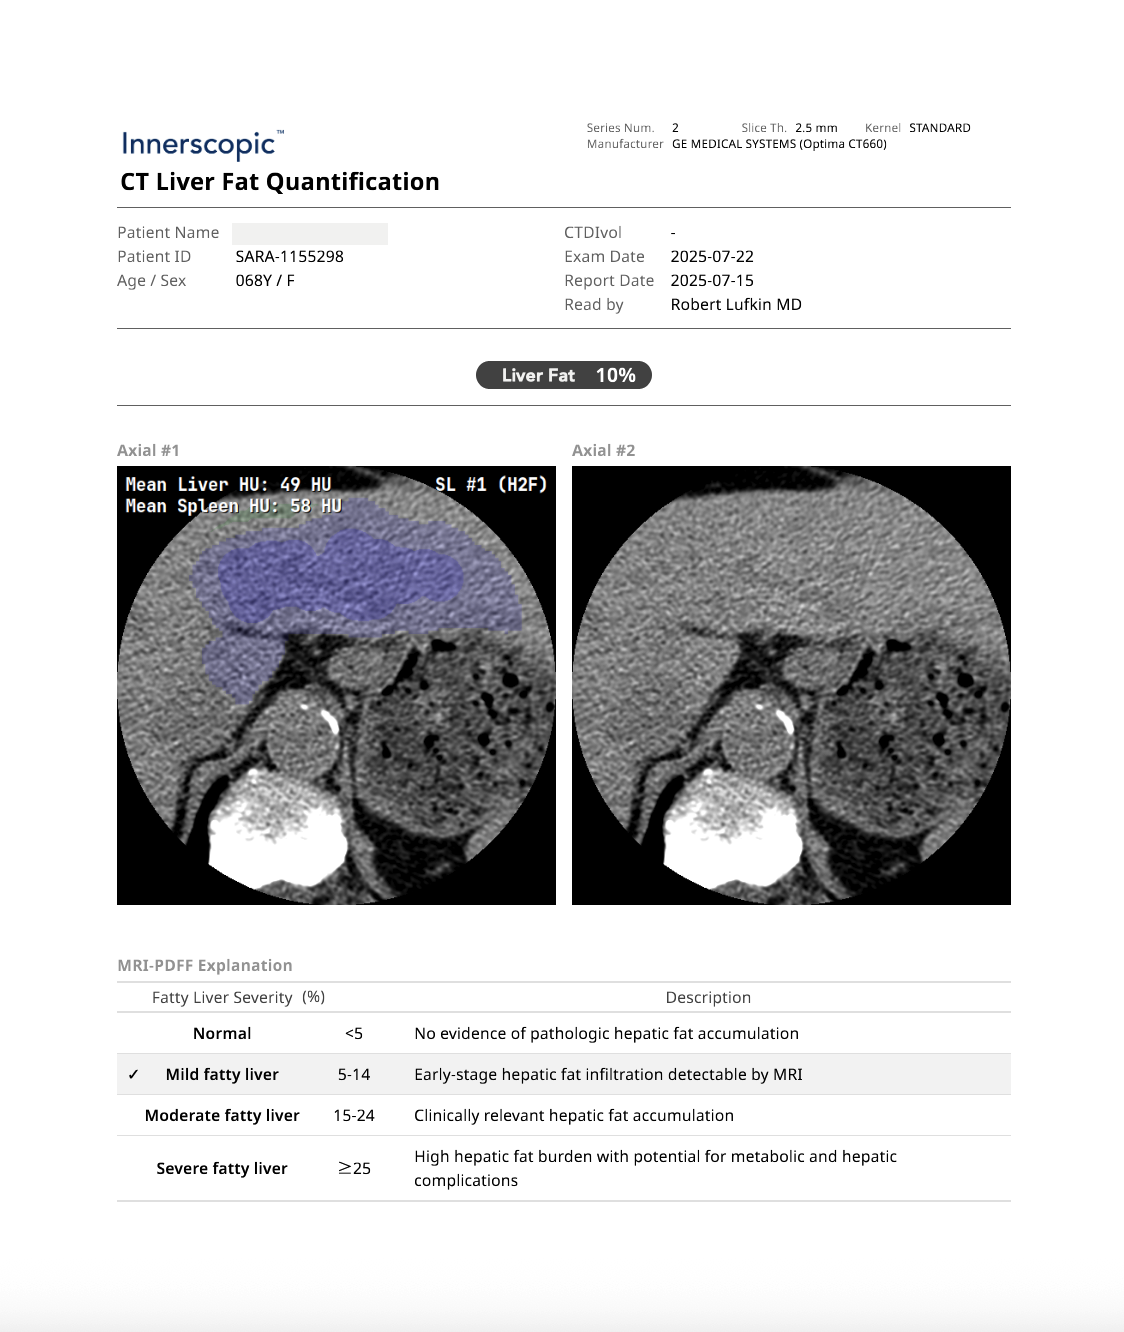

CT LIVER FAT QUANTIFICATION